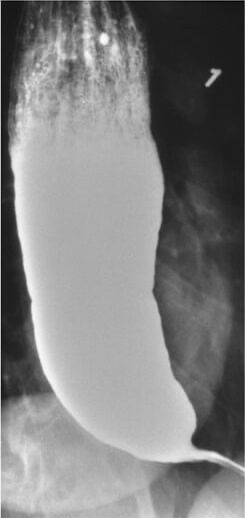

- Röntgen Breischluck → typisches Bild: „Bird-beak sign“ (Vogelschnabel-Form)

- Achalasie → UÖS zu fest, keine Peristaltik → Vogelschnabel